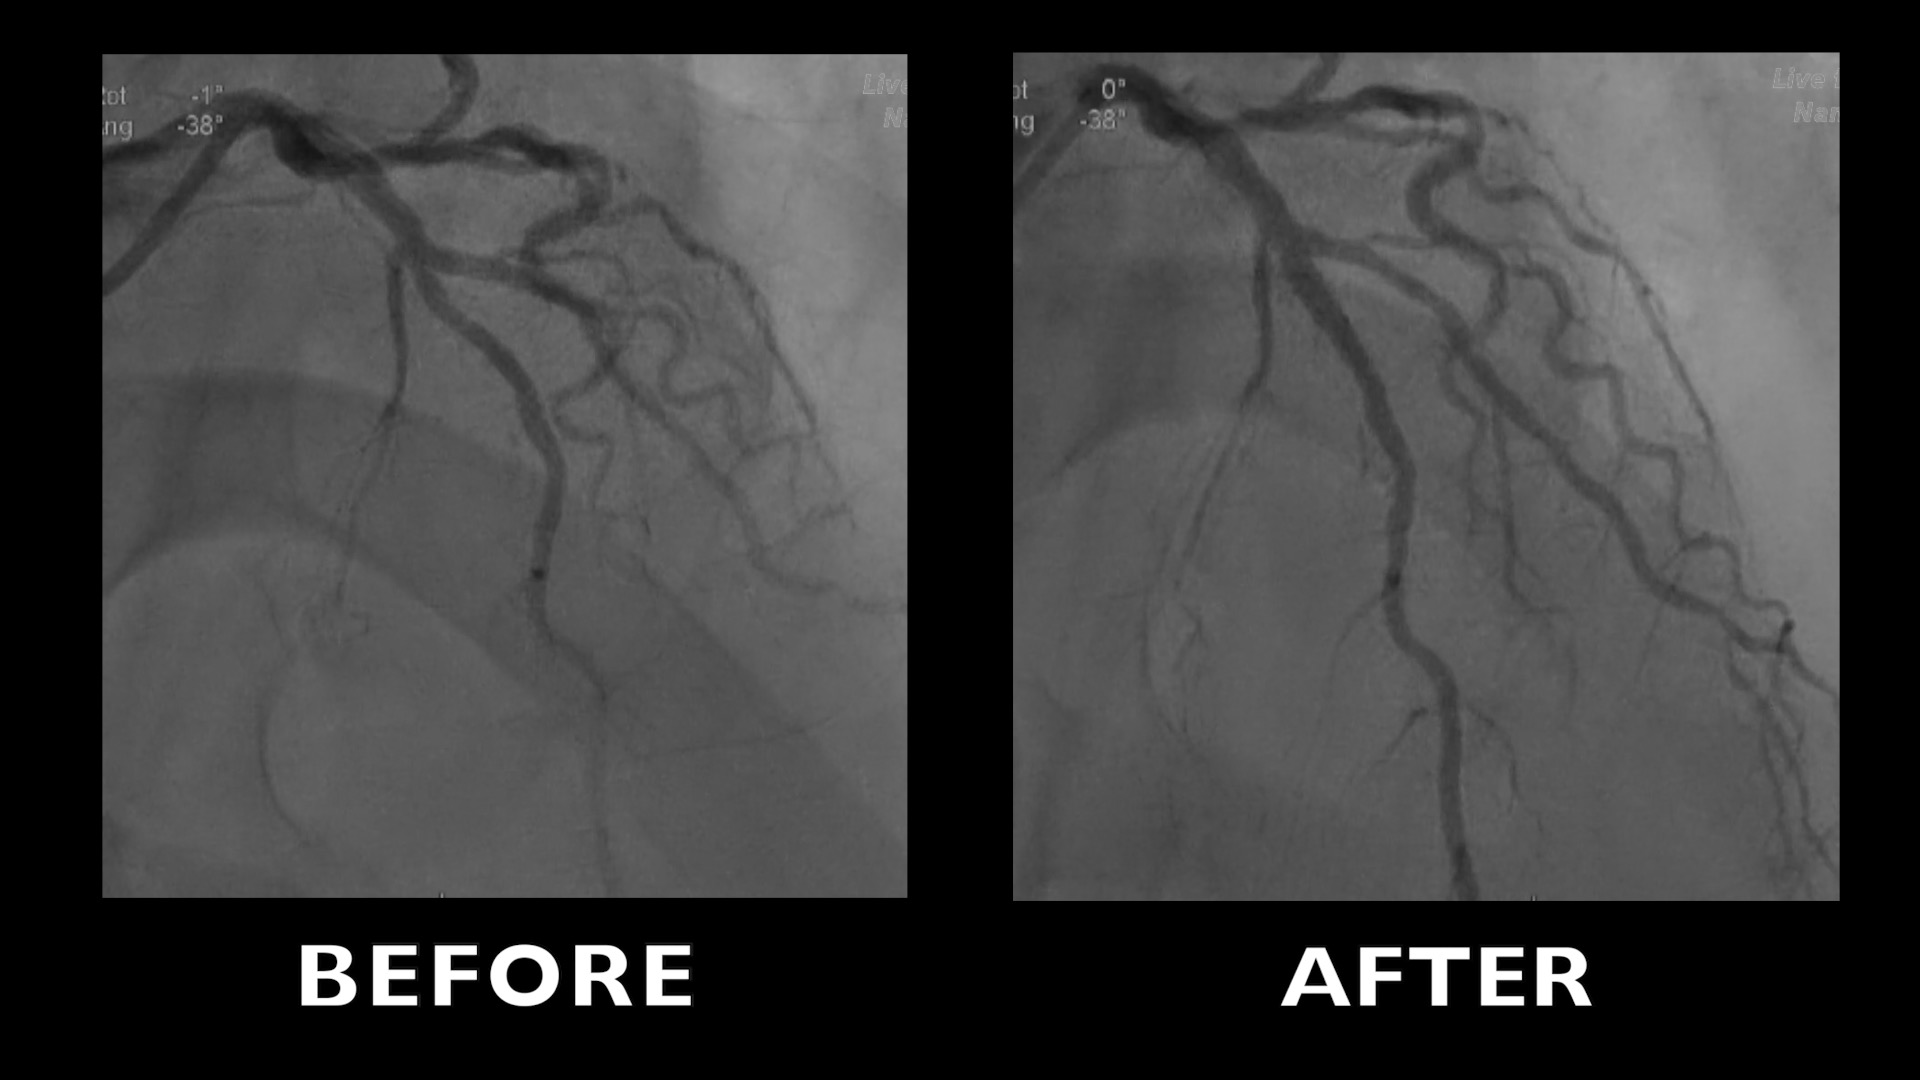

Left main coronary stenting by polymer free stent. OCT evaluation

The coronary angiography reveals a severe left main trunk stenosis on its distal part and an intermediate stenosis of the proximal part of the left anterior descending artery.

OCT evaluation of left main stenosis

LAD proximal stenting

Left main stenting (4x15)

Post stenting dilatation (4.5 mm non-compliant balloon)

Post stenting evaluation by OCT